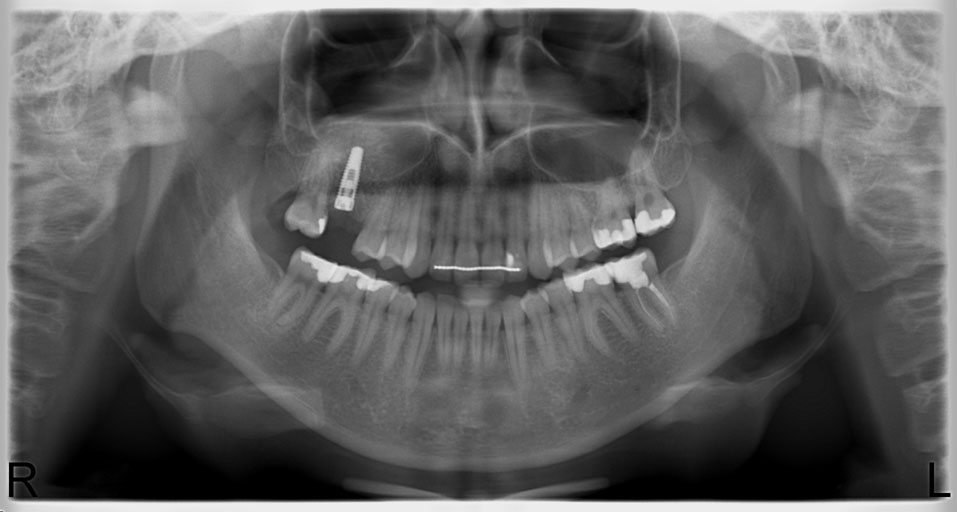

Zdjęcia ortopantomograficzne

Zdjęcia ortopantomograficzne są wykorzystywane w stomatologii zachowawczej, chirurgii, implanto-protetyce, ortodoncji oraz w leczeniu chorób przyzębia.

Pozwalają na uwidocznienie jednocześnie wszystkich struktur anatomicznych czyli: zębów, stawów skroniowo-żuchwowych, kości szczęk i żuchwy. Na zdjęciach ortopantomograficznych obserwujemy stopień mineralizacji i kierunek wyrzynania się zębów, nieprawidłowości w budowie korzeni, umiejscowienie zębów zatrzymanych oraz położenie korzeni zębów względem zatok szczękowych. Zdjęcia te pozwalają także na dokładną ocenę stanu przyzębia.

W Naszym gabinecie posiadamy w pełni cyfrowy aparat ortopantomograficzny firmy Morita, którego głównymi cechami są:

- trzykrotnie krótszy czas ekspozycji w porównaniu z innymi aparatami

- sześciokrotnie mniejsza dawka w porównaniu z aparatami analogowymi

- doskonała jakość zdjęć

- trzy programy pracy (standardowy ortopantomogram, ortopantomogram dla dzieci, zdjęcie czynnościowe stawów skroniowo-żuchwowych)

- bardzo proste ustawianie pacjenta za pomocą trzech wskaźników laserowych